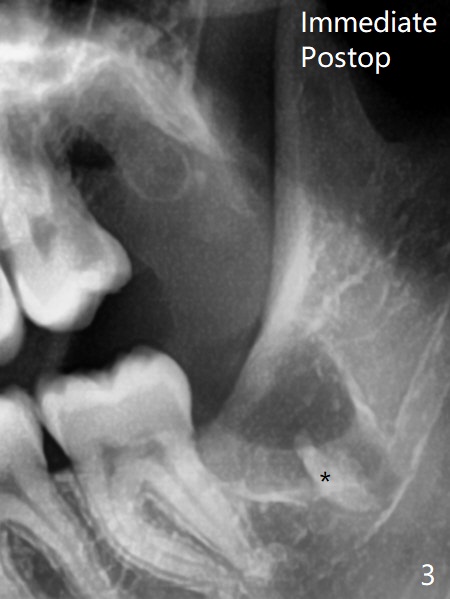

Postop panoramic X-ray (Fig.3) is taken before suture at #17 with suspicion of a retained root tip (*).